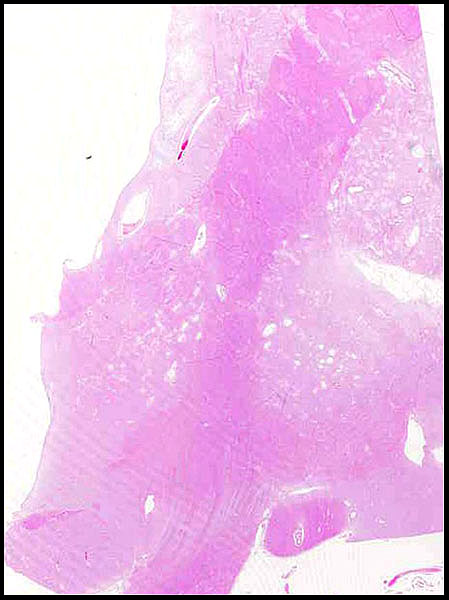

Estado lacunar de ganglios de la base